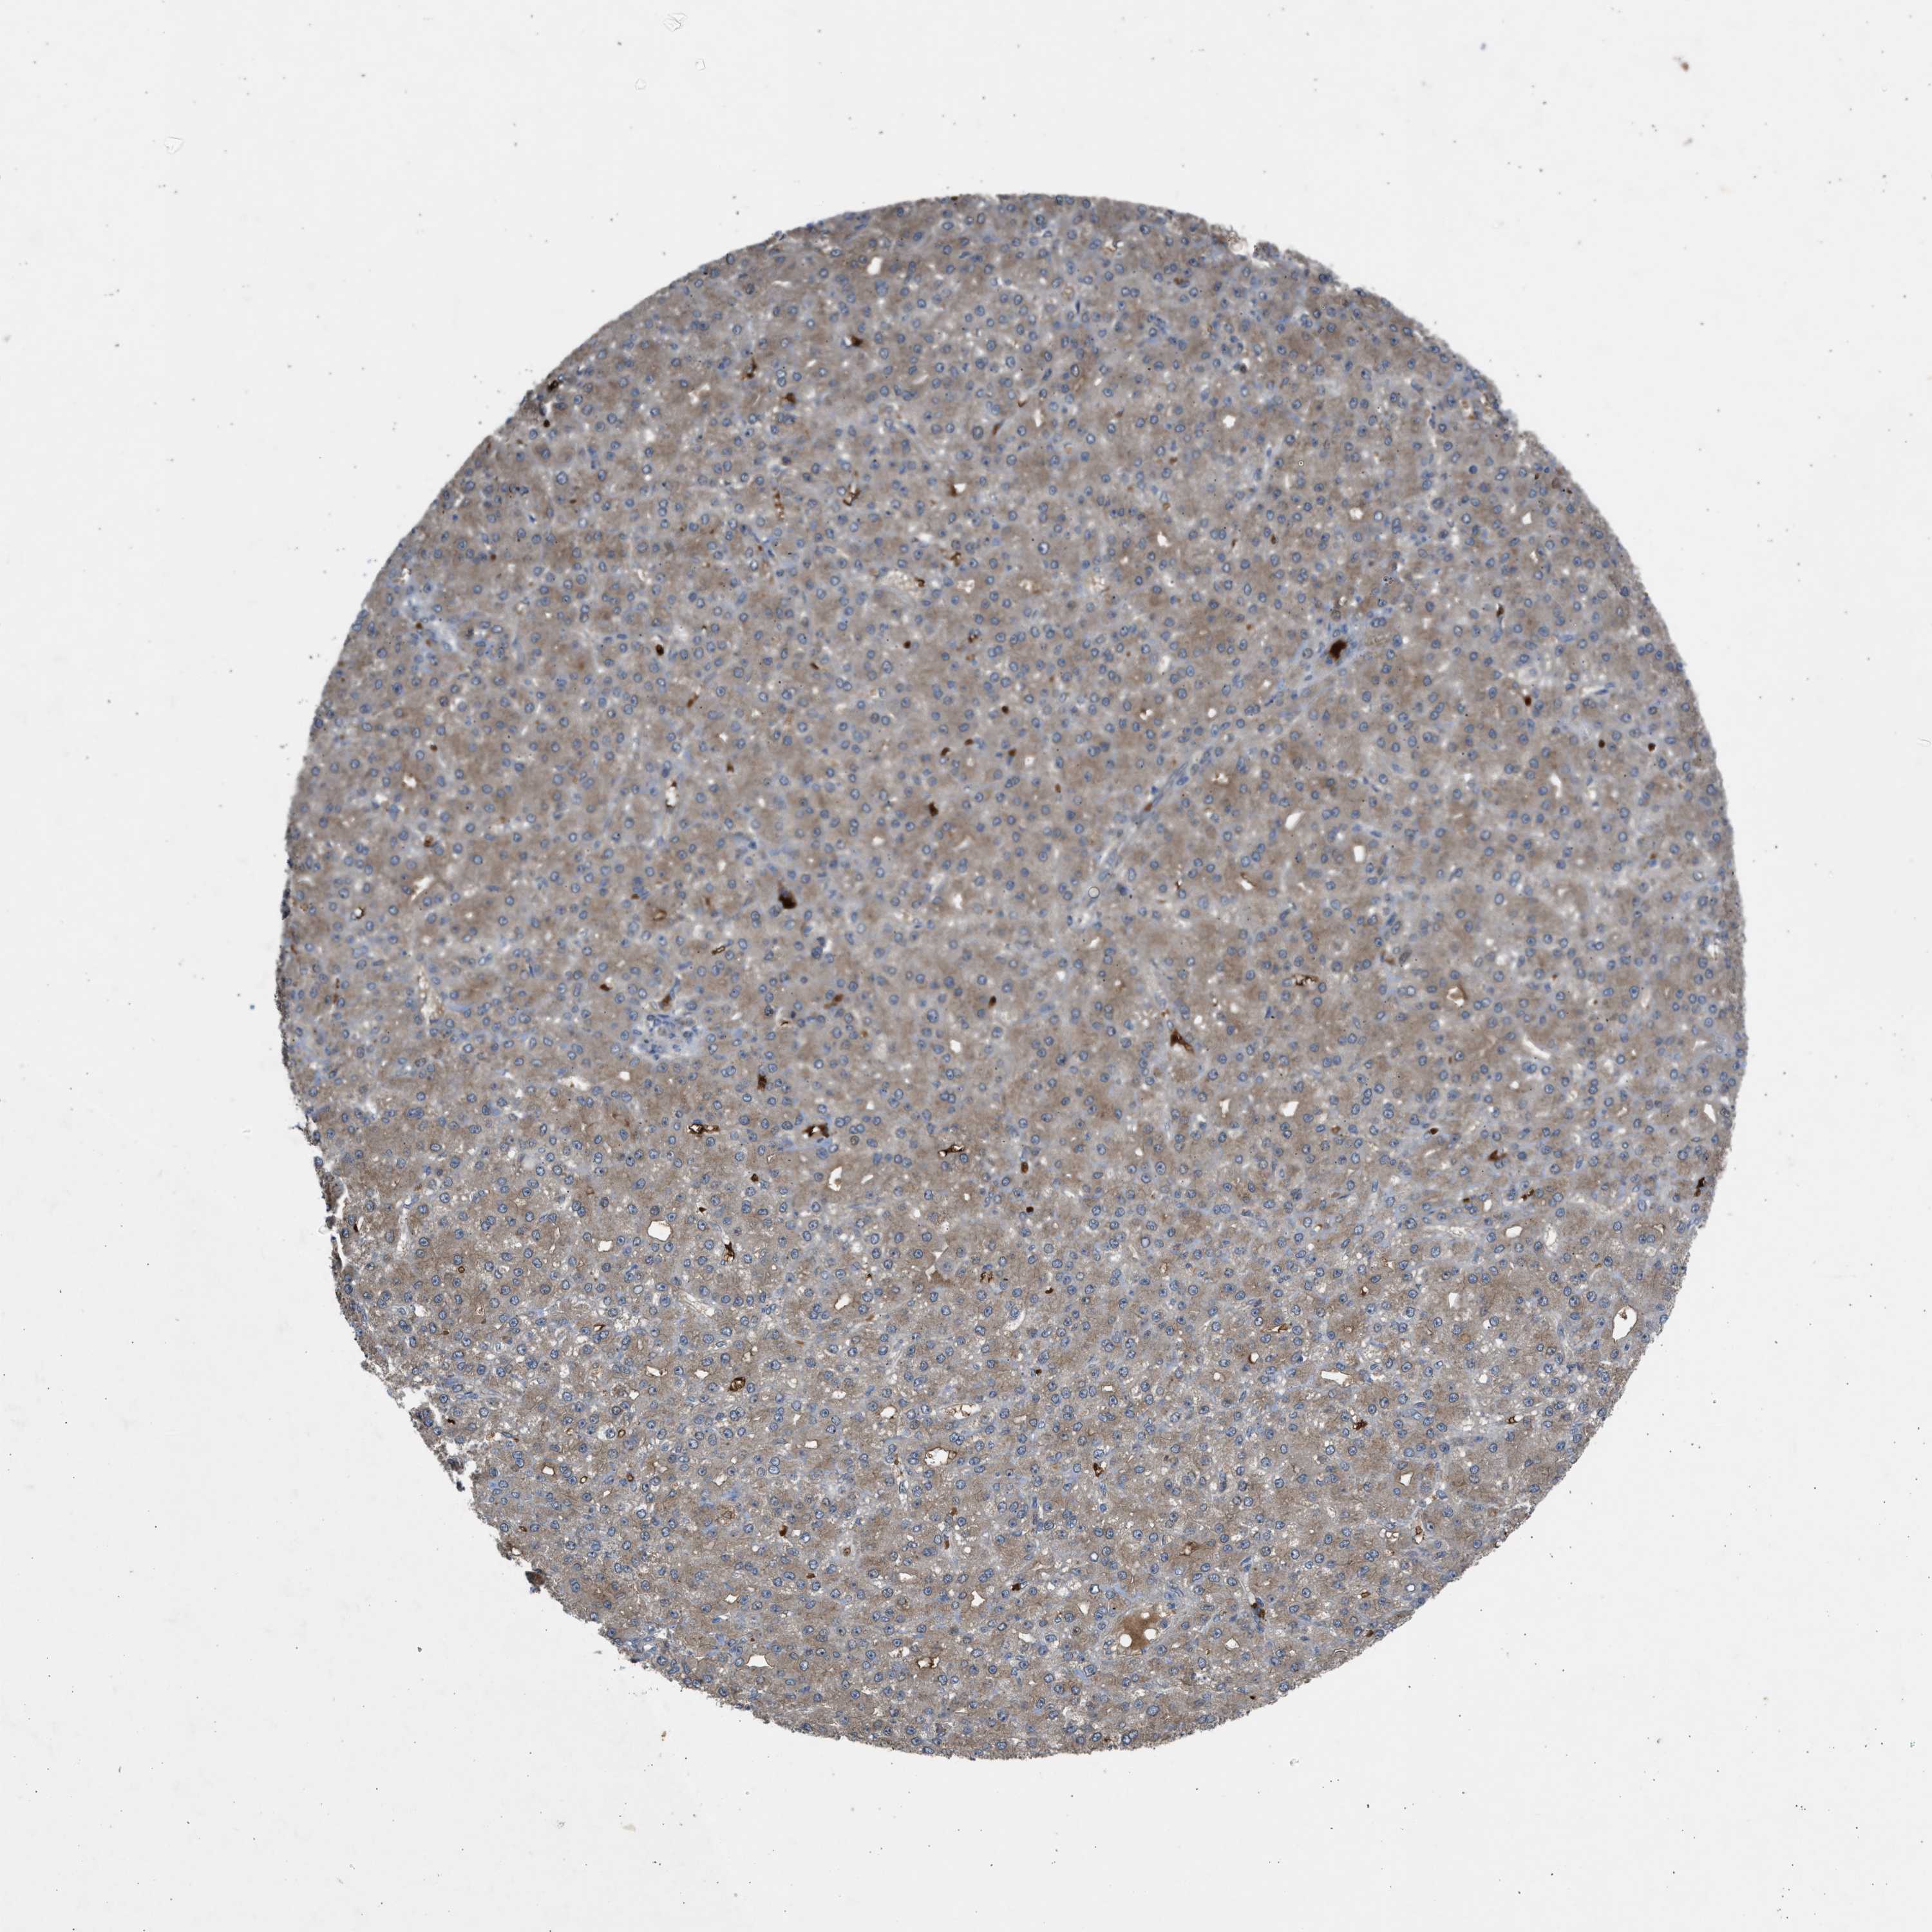

LIVER CANCER - Protein expressioni

A mouse-over function shows sample information and annotation data. Click on an image to view it in a full screen mode. Samples can be filtered based on level of antibody staining by selecting one or several of the following categories: high, medium, low and not detected. The assay and annotation is described here.

Note that samples used for immunohistochemistry by the Human Protein Atlas do not correspond to samples in the TCGA dataset.

Antibody stainingi

Antibody staining in the annotated cell types in the current human tissue is reported as not detected, low, medium, or high, based on conventional immunohistochemistry profiling in selected tissues. This score is based on the combination of the staining intensity and fraction of stained cells.

Each image is clickable and will lead to virtual microscopy that enables deeper exploration of all samples and also displays staining intensity scores, fraction scores and subcellular localization as well as patient and tissue information for each sample.

Antibody CAB018561

Staining

High

Medium

Low

Not detected

Intensity

Strong

Moderate

Weak

Negative

Quantity

>75%

75%-25%

<25%

None

Location

Nuclear

Cytoplasmic/membranous

Cytoplasmic/membranous,nuclear

Cholangiocarcinoma

Carcinoma, Hepatocellular, NOS